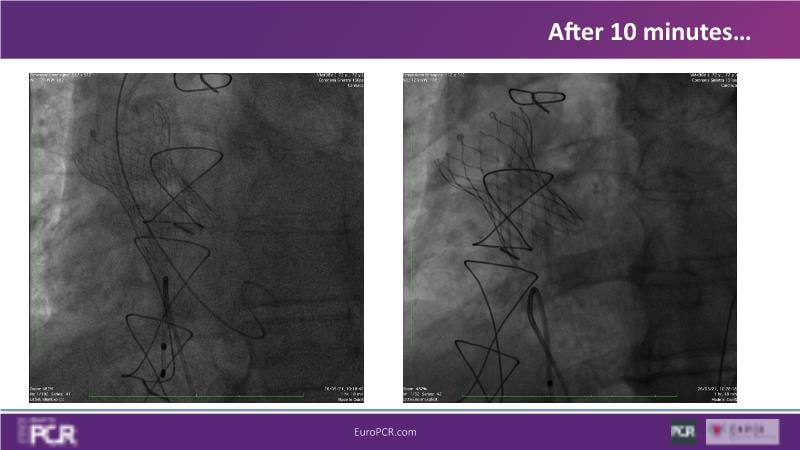

Discover the key factors to consider in selecting the optimal valve and implant technique for transcatheter aortic valve implantation (TAVI) to achieve optimal procedural outcomes. Gain insights into the impact of device choice and implantation technique on coronary access following TAVI and learn valuable strategies for tailoring your TAVI technique to complex scenarios, including bicuspid aortic valves, large and calcified anatomies, and ensuring coronary access.

- To learn how to tailor your TAVI technique to complex situations: bicuspid aortic valves, large, calcified anatomies and coronary access